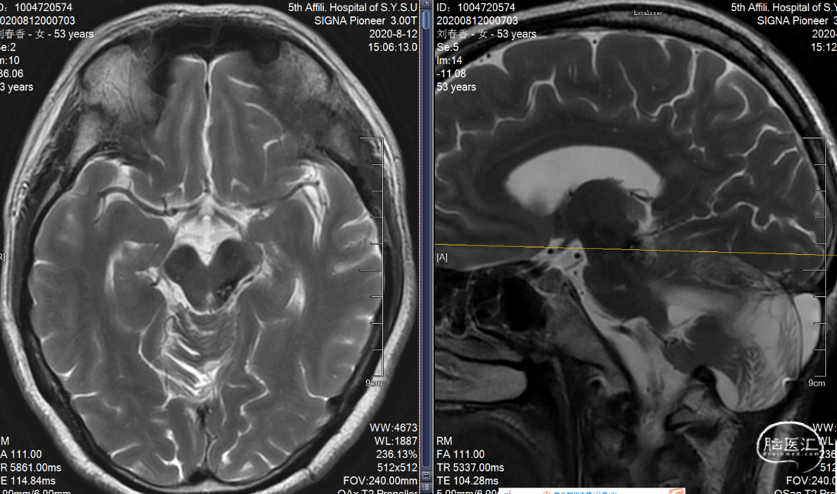

患者,女,27岁,发现脑室旁海绵窦状血管瘤,是一种多发的海绵状血管瘤。反复出血两次,用显微镜手术。9天后复查,可见一定血丝,2个月后复查,很干净,病人无明显病灶。今年复查见对侧丘脑有一血肿,手术难度大。